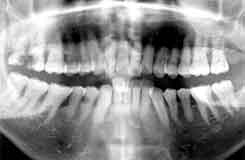

| 初診時 パノラマ | 10年後 パノラマ |

| 中程度の歯周疾患進行を認めるが、年齢の割には良好 62歳 女性 |

1本の歯も失うことなく10年経過 |

初診時口腔内およびX線所見:

清掃状態は比較的良好で、全体に中程度の歯槽骨吸収を認めるが年齢の割には進行が軽度で

あった。ただし、歯肉縁下歯石の沈着が著しく、76|67部の歯槽骨吸収は1/2以上で特に

|7の動揺は著しい。